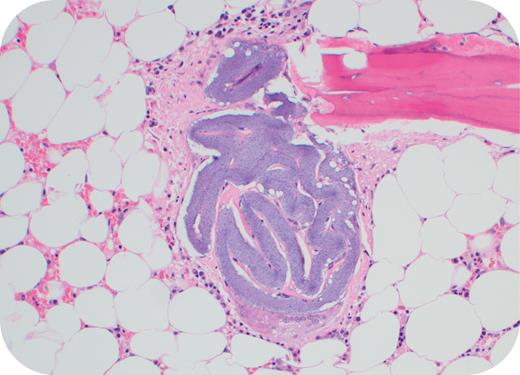

A 73-year-old man had a bone marrow evaluation for severe anemia (hemoglobin, 6.9 g/dL; white blood cell count, 5.8 × 109/L; platelet count, 156 × 109/L). Clinically, he was diagnosed with multiple comorbidities including hypertensive heart disease, heart failure, peripheral vascular disease, and chronic kidney disease. Past surgical history included aortic valve replacement for aortic regurgitation, right coronary artery stenting, femoral popliteal bypass grafting, and left total nephrectomy. The bone marrow was normocellular with no dysplasia. However, an acellular deposit of nonrefractile, nonpolarizable granular basophilic material surrounded by few giant cells was incidentally identified within a vascular space (bone marrow biopsy; hematoxylin and eosin stain; original magnification ×400). The identified foreign body was likely a hydrophilic polymer embolus resulting from the patient’s previous catheterizations.

Hydrophilic polymer coatings are frequently used in medical devices. These can partially fragment and embolize to small-caliber vessels and are often seen on postmortem examination. Recognition of these polymers on histologic evaluation is of clinical importance, as morphologic findings may be subtle but multifocal embolization can be fatal. Although no associated infarct or necrosis was seen in our bone marrow specimen, these patients are at risk of sequelae of iatrogenic embolization such as ischemia, gangrene, or stroke.